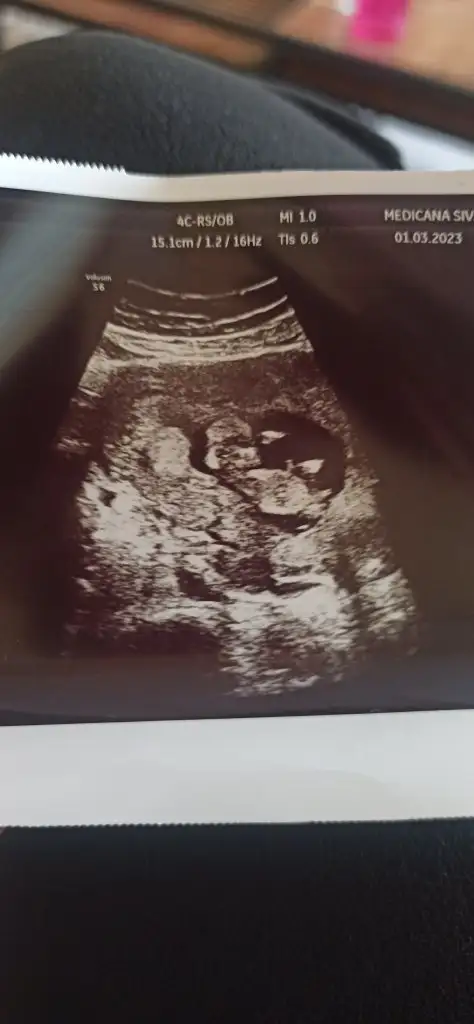

Kızlar bak miniciğim daha gözükmüyoruz bile ama dualarınız bekliyorum

Bugün şu toxo sordum kızlar bir testi daha varmış oranına göre ilacı var dedi rabbime şükürler olsun biraz minnakız 7+0 olması lazım geç döllenme olmuş dedi bunada şükür hamdolsun resim koyarım pek gözükmüyoruz gerçi nefesimi tutarak kalbini duyduk Allah’ıma hamdolsun hepimiz sağlıkla kucağımıza alalım Rabbimin eli üzerimizde olsun